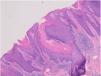

Unos meses antes de la última consulta, el paciente desarrolló placas verrugosas en la región perianal y glútea, también intensamente pruriginosas. En la exploración física se observaron 3 placas hiperqueratósicas eritematosas bien delimitadas en el escroto (fig. 1a) y en la región perianal (fig. 1b), de aproximadamente 2cm cada una. No se observaron lesiones similares en otras partes del cuerpo durante la exploración. Las biopsias por afeitado de las lesiones perianales mostraron hiperplasia epidérmica psoriasiforme con presencia de varias columnas de paraqueratosis con hipogranulosis (fig. 2). No había rasgos indicativos de malignidad.

La presencia de una lamela cornoide es el hallazgo histopatológico característico de todas las variantes de poroqueratosis; una columna de paraqueratosis que se correlaciona con los límites hiperqueratósicos de las lesiones. Sin embargo, a diferencia de otras variantes de poroqueratosis, las láminas cornoides que se observan en la PP no se limitan a los bordes, sino que se extienden por toda la lesión1.